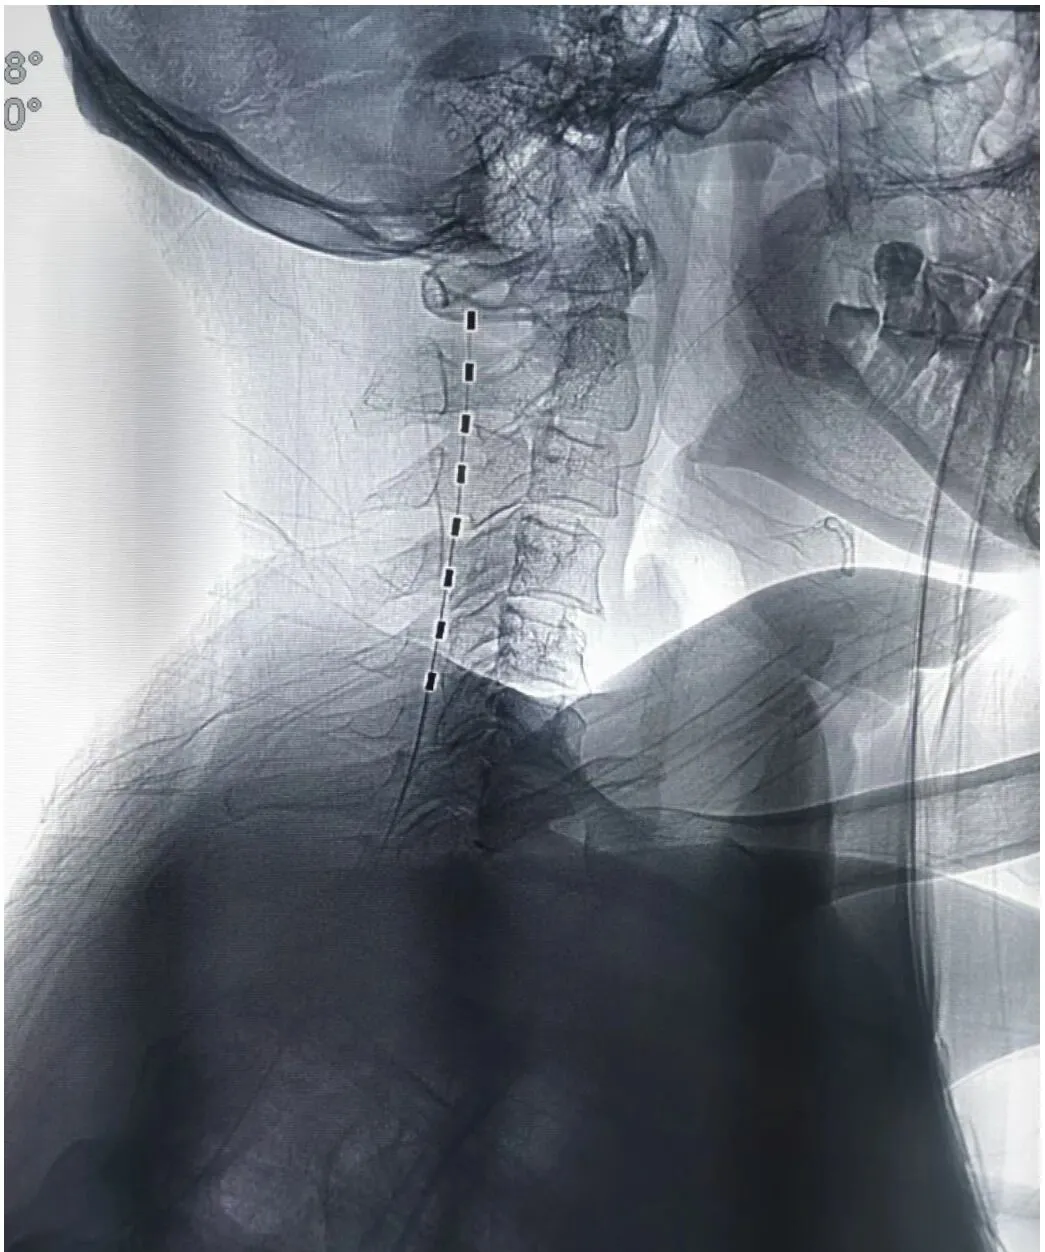

六、脊髓神经电刺激植入术

脊髓神经电刺激植入术是指将脊髓刺激电极置于椎管的硬膜外腔后间隙,刺激电极产生电场,刺激脊髓后部的上行结构:脊神经背根、脊髓后角神经元、脊髓丘脑束等,通过电流刺激脊髓后柱的传导束和后角感觉神经元,阻断/干扰疼痛信号通过脊髓向大脑传递,从而达到治疗疼痛或其它疾病目的的一种治疗方法。电刺激植入的适应症: 复杂性局灶性疼痛综合征(CRPS) 、神经源性疼痛(神经病理性疼痛) 、幻肢痛/残肢痛、带状疱疹后遗神经痛、脊髓损伤 、 糖尿病周围神经痛、周围缺血性疼痛 、血栓闭塞性脉管炎、糖尿病足等慢性疼痛。

神经电刺激术的优点: